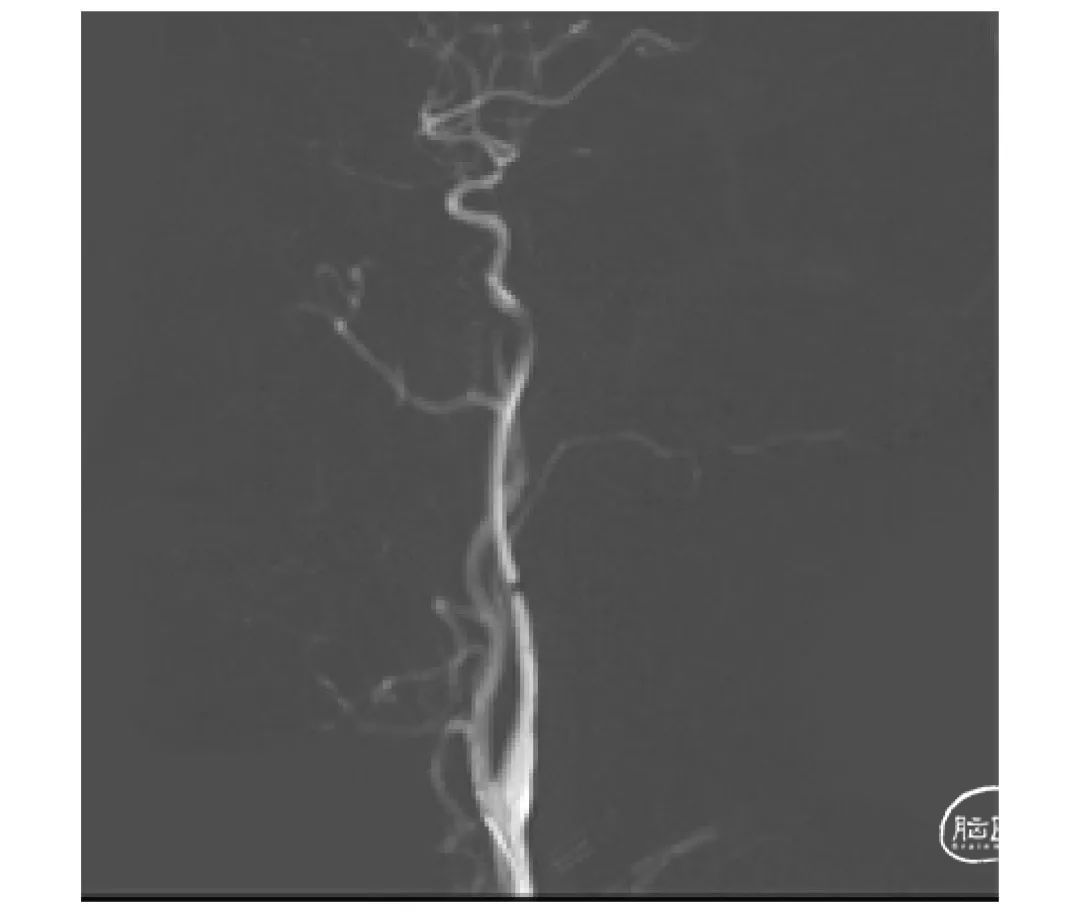

上海心玮医疗科技股份有限公司(股票代码:06609.HK)成立于 2016 年,公司致力于提高创新医疗技术的可及性,守护生命健康。六年时间,心玮医疗在神经介入领域开拓性地打造了国内首个卒中治疗及预防一站式解决方案,拥有从急性缺血性卒中和神经血管狭窄治疗、缺血性卒中预防、出血性卒中治疗到介入通路器械的全产品管线,申请专利超过 100 项,产品年产能超过 15 万件,销售渠道覆盖国内超过 30 个省(含直辖市和自治区)的 1400 多家医院。